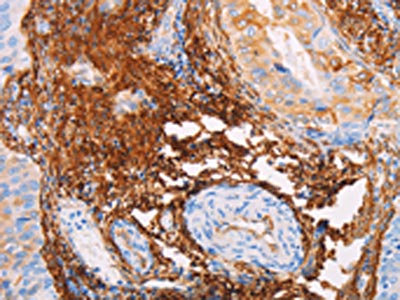

The image on the left is immunohistochemistry of paraffin-embedded Human colon cancer tissue using CSB-PA546098(TGM2 Antibody) at dilution 1/15, on the right is treated with fusion protein. (Original magnification: ×200)